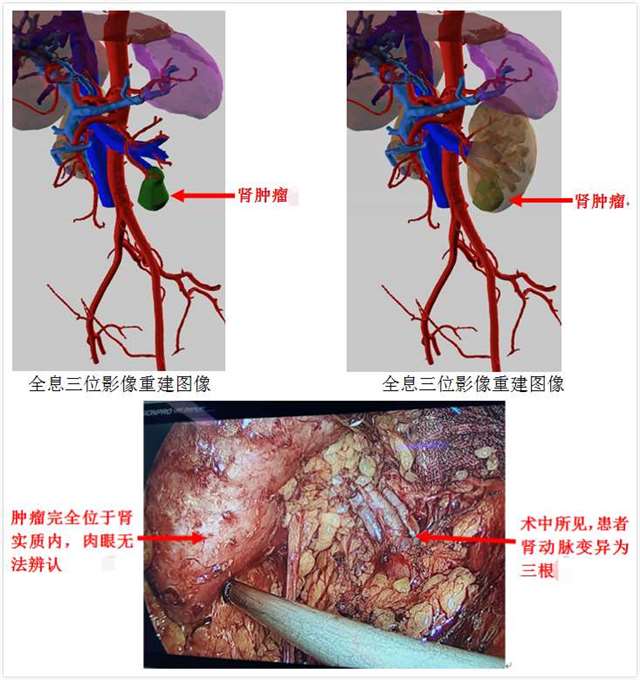

刘川教授和胡自力教授通过仔细阅读患者影像学资料,发现患者肾脏肿瘤是一个内生型的肿瘤,而且位于肾脏的核心部位——肾门部。该部位实施保留肾脏的肿瘤剜除术难度极高,稍有不慎有可能损伤血管造成大出血,或破坏肾脏集合系统,造成尿液外渗。内生性肿瘤从外观上看肾脏形态完全正常,无法看到其内部肿瘤,在手术时外科医生可能无法分辨肿瘤与正常组织,导致手术无从下手或手术过程中肿瘤切除不干净。此外,患者体重达190斤,过量的肾周脂肪与肾包膜严重粘连会导致肾肿瘤边界不清、暴露困难,粘连严重的脂肪组织血供丰富,容易发生出血,增加了手术难度。CTA提示患者肾动脉血管变异较大,有三支动脉供血且三支肾动脉包绕肾静脉,无疑又增加了手术难度。

在患者的殷殷期待下,刘川教授和胡自力教授采用全息三位影像重建技术,仔细评估患者肾脏肿瘤与肾静脉、主动脉及输尿管之间的关系,经与麻醉科讨论后,为患者制定了详细的手术方案,凭借以往开展过多例类似手术的经验,决定行低温冰水下的后腹腔镜下肾肿瘤剜除术,既能最大程度的保留肾功能,又能完整切除肿瘤且创伤小。